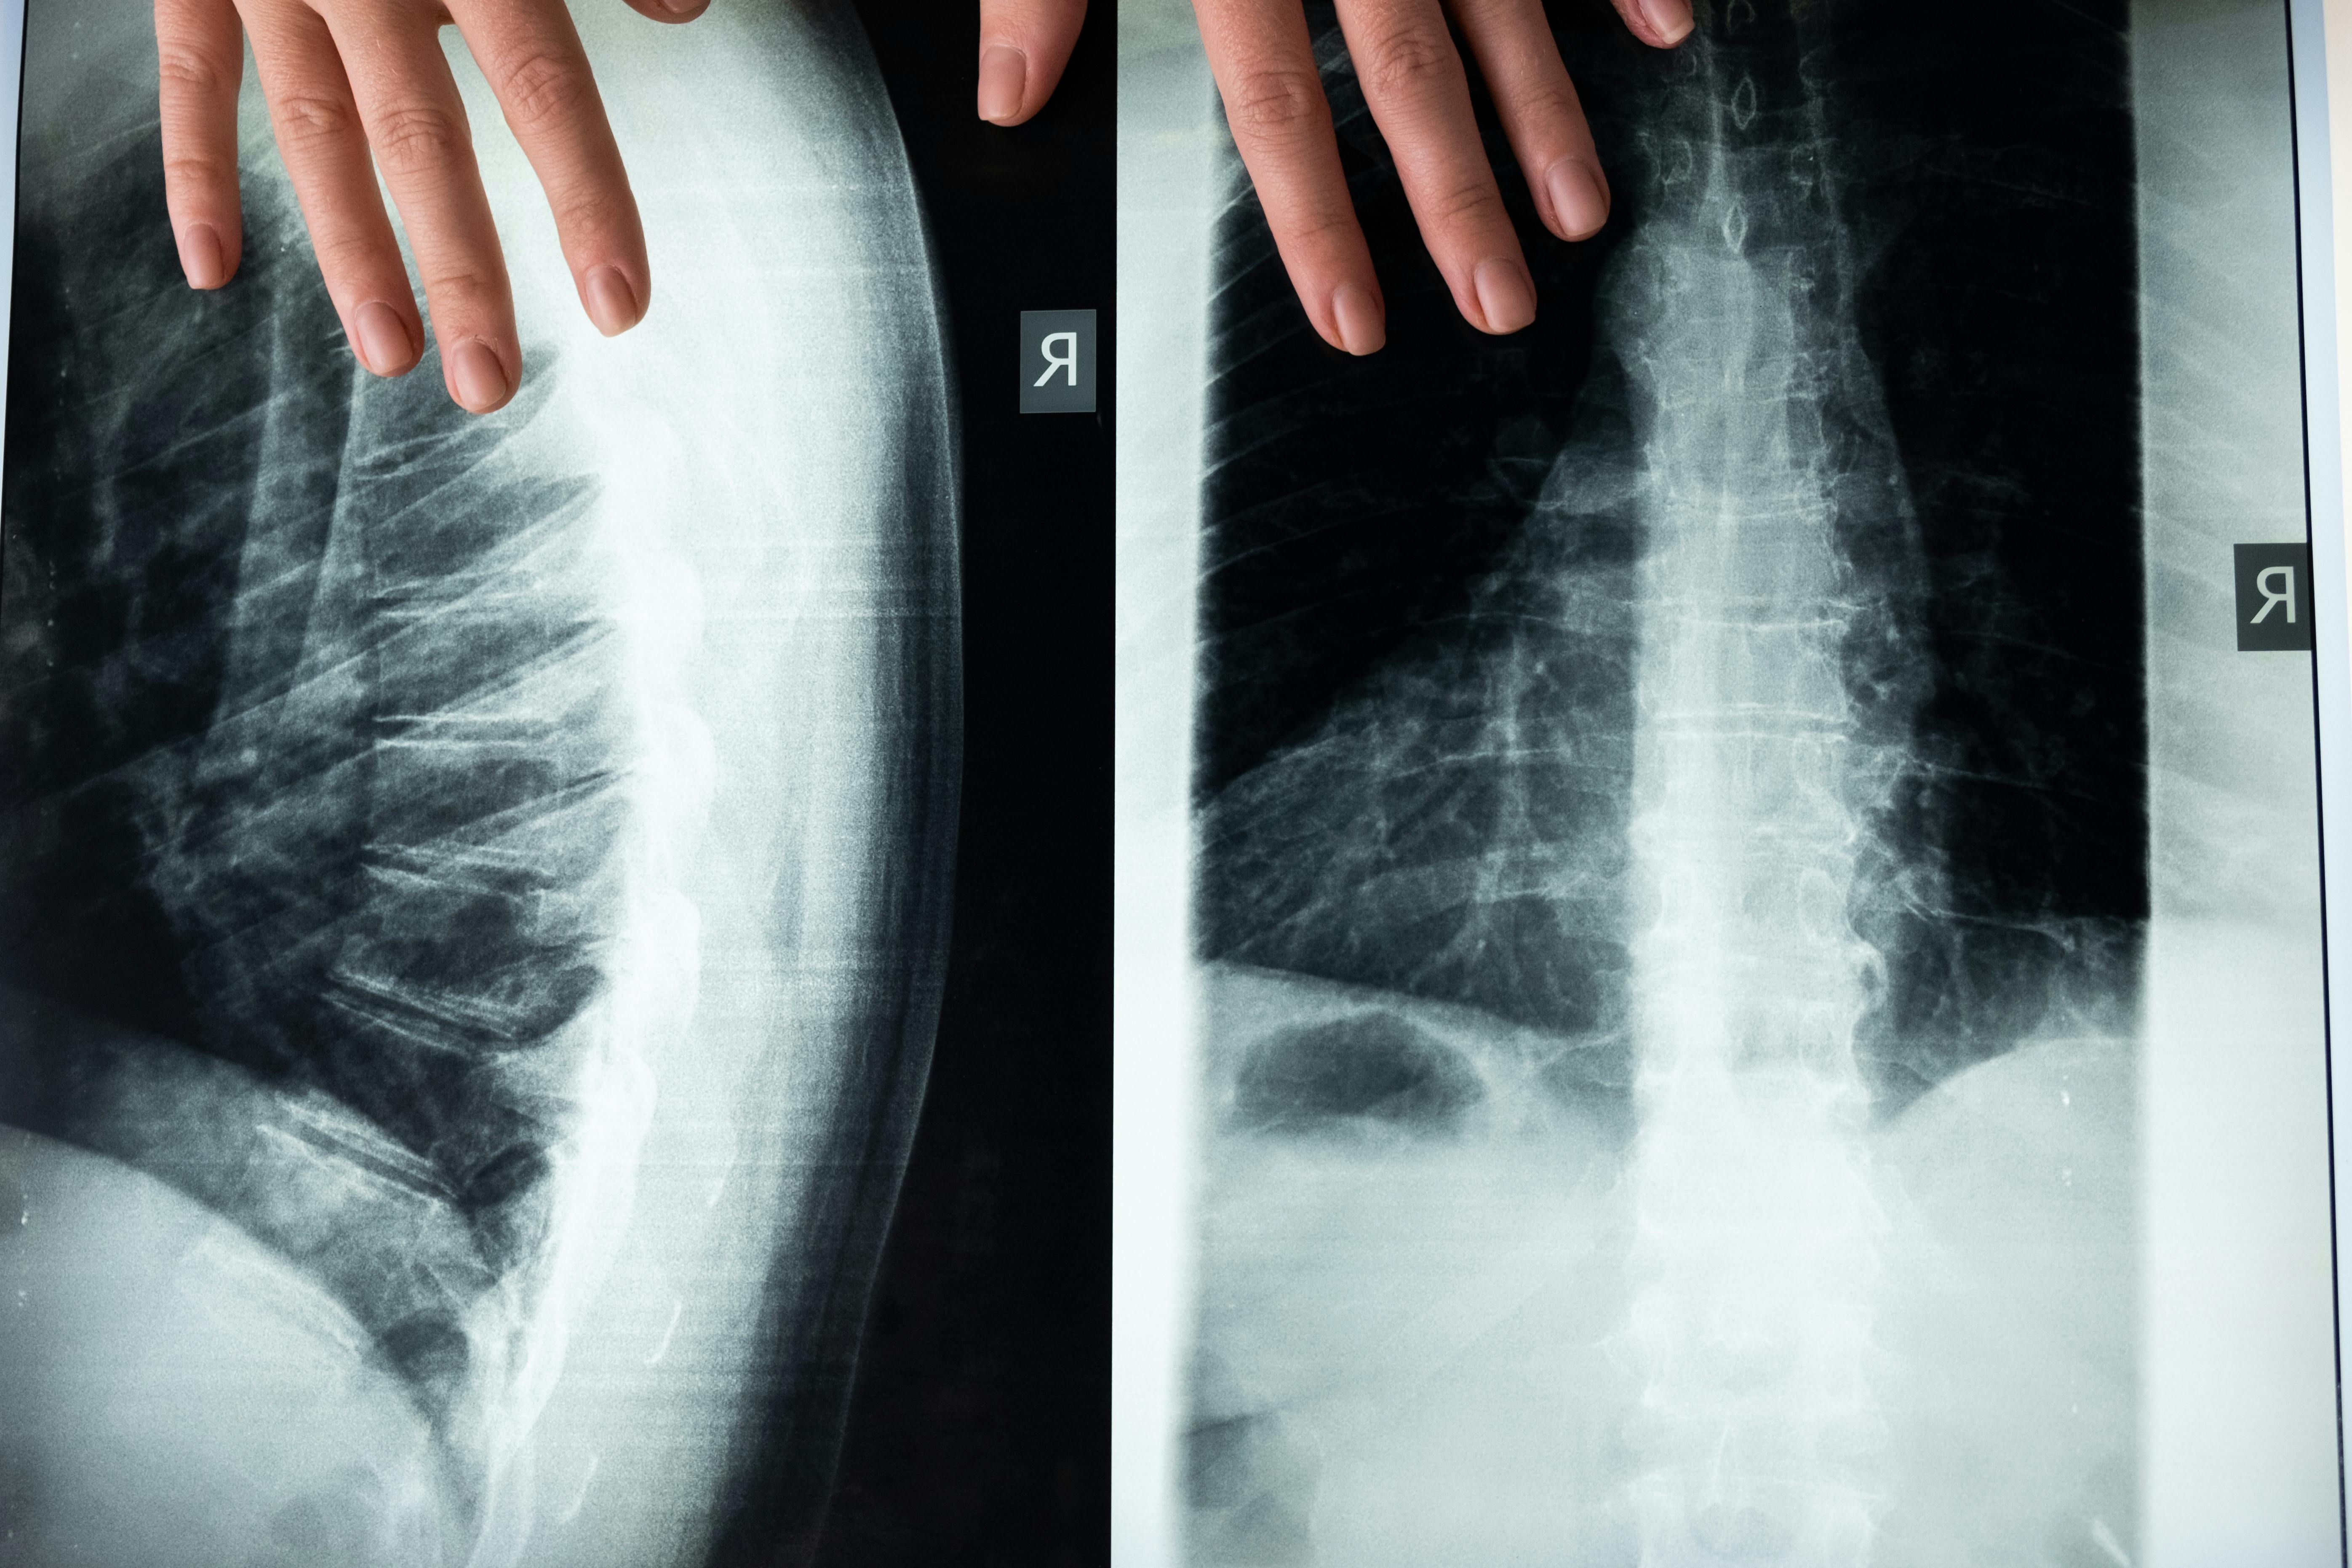

척추측만증은 척추가 정상적인 위치에서 옆으로 휘어지는 상태를 말합니다. 이 상태는 종종 청소년기에 발견되며, 경미한 경우가 많지만 심한 경우에는 통증이나 호흡 문제를 유발할 수 있습니다.

척추측만증의 증상과 관리 방법에 대해 자세히 알아보겠습니다